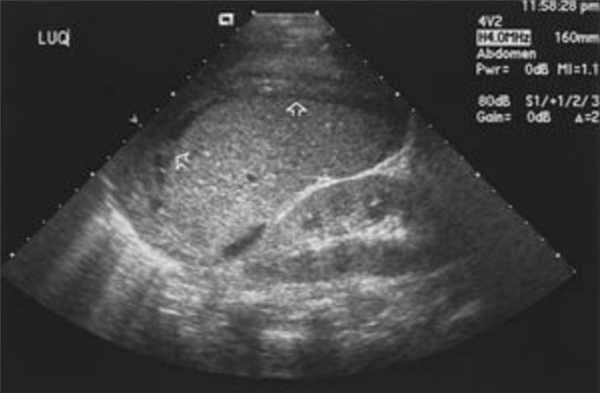

Диагностика селезенки при помощи УЗИ брюшной полости

УЗИ этого органа позволяет выявлять заболевания на самой ранней стадии. Ультразвуковое обследование показывает следующие параметры органа:

- Размеры органа — в норме длина не превышает 13 см, ширина — 8 см и толщина 5 см;

- Эхогенность — у здорового органа она средняя. Отсутствие эхогенности указывает на абсцесс, а гиперэхогенность вызывается накопившимися пузырьками газа;

- Форма селезенки — в норме она имеет форму полумесяца, но различные новообразования делают форму округлой, а контуры неровными;

- Повреждение структуры селезенки — такое происходит при инфаркте — кровоизлиянии, вызванном тромбозом артерии или вены. УЗИ отображает пониженную эхогенность, нечеткие контуры и треугольную форму органа;

- Травмы селезёнки — при разрыве вследствие тупой или острой травмы живота образуется гематома. На экране монитора это отображается отсутствием эхогенности на месте травмы, а также визуализацией свободной жидкости;

- Кисты — они имеют четкий контур и овальную форму, поэтому легко визуализируются аппаратом УЗИ. Внутри кисты находится жидкость, поэтому она имеет анэхогенную структуру.